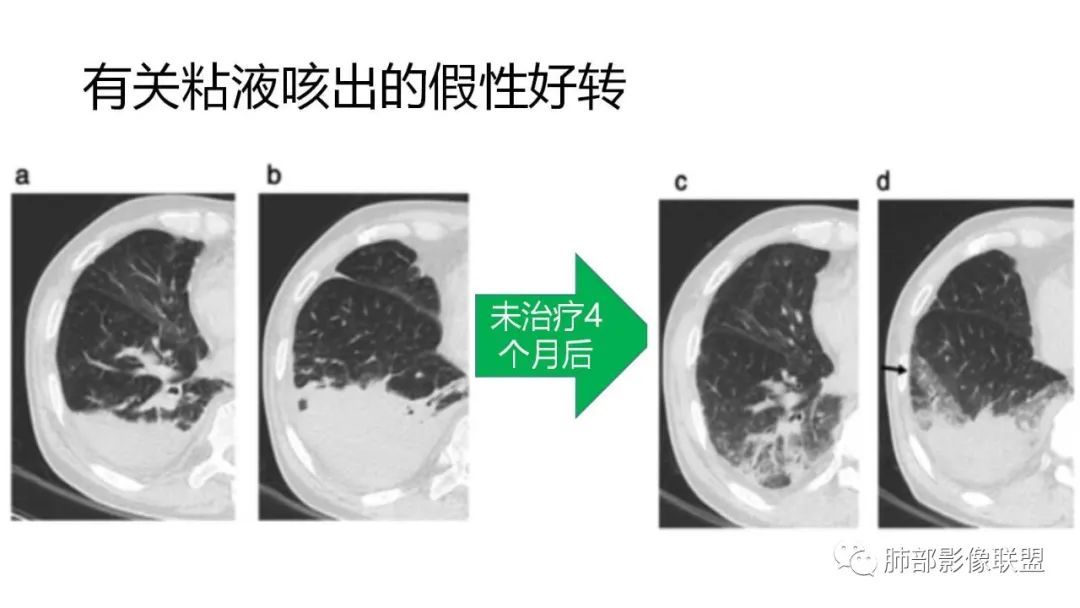

9.粘液腺癌的变化规律:结节缓慢发展而来,向周围播散形成斑片后可快速进展,有时支气管镜后或粘液排出后局部可形成好转的假象。病灶可沿肺泡和支气管播散。

4.回到本例,左下肺病变两次好转,均未经过肿瘤治疗,第一次是支气管镜后,第二次是当其他病变都在进展的情况下,左下肺病变范围反而缩小趋于浅淡。